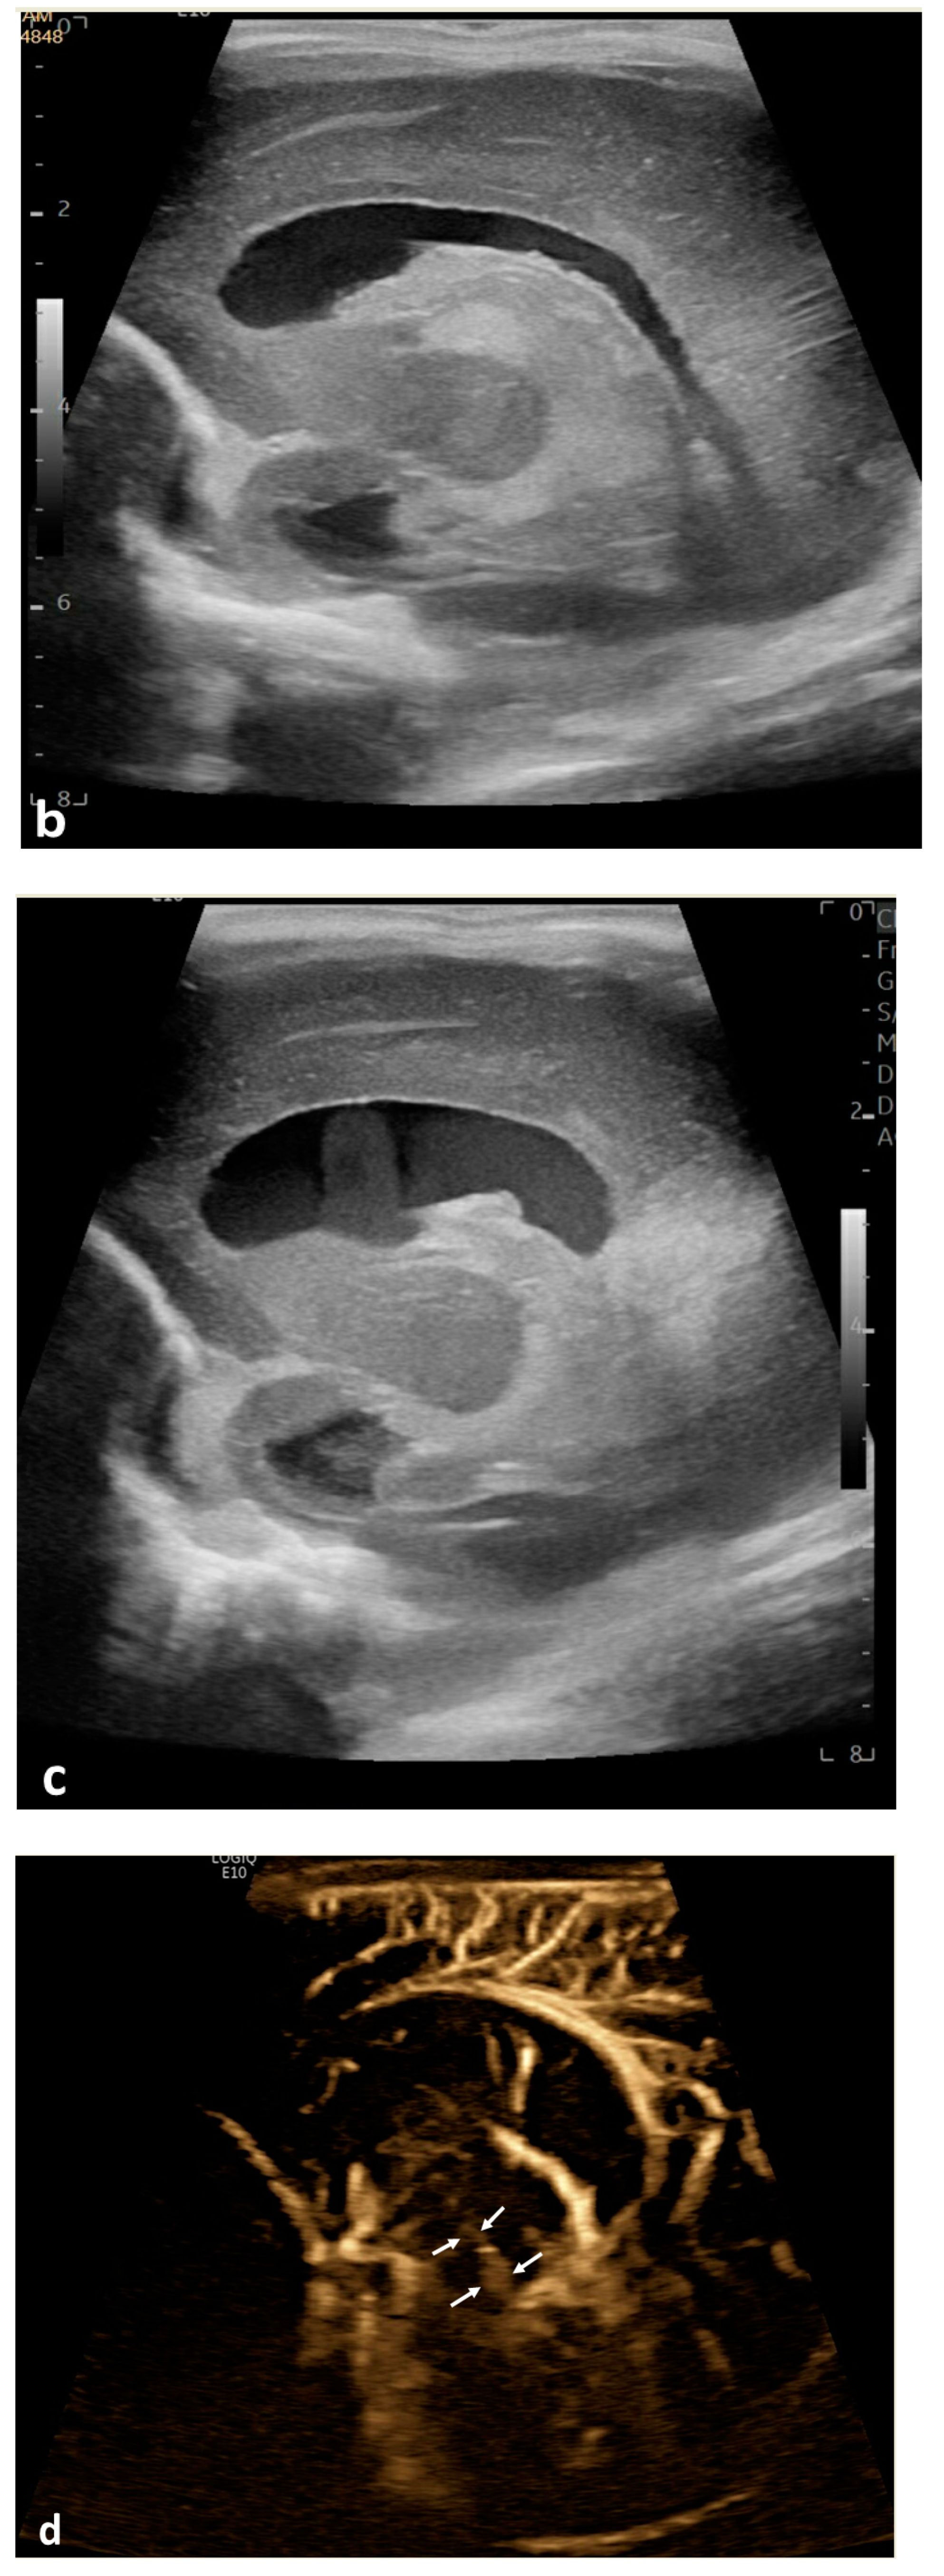

Twenty patients (19.8%) demonstrated apparent CSF flow detectable using MVI in at least one of the ventricular structures: 11 (10.9%) in the third ventricle, 16 (15.8%) in the cerebral aqueduct, and 17 (16.8%) in the fourth ventricle (Figure 1 and Figure 2). Of these 20 patients, 13 had IVH as visualized in grayscale US; flow direction was detected as craniocaudal in 15% (n = 3) of patients, caudocranial in 70% (n = 14), and bidirectional in 15% (n = 3) (Supplemental S1 and S2; Table 1). The IRR for detection of CSF flow was 0.662, p < 0.001.

Figure 1.

Cerebrospinal fluid (CSF) flow visualized in the ventricular system. A 15-day-old term girl with a history of bilateral grade III intraventricular hemorrhage and hydrocephalus underwent brain ultrasound. This patient also had cardiovascular comorbidities, including dextro-transposition of great arteries, ventricular septal defect, and tricuspid regurgitation. (a–c) Sagittal B-Flow demonstrates turbulent caudocranial CSF flow in the cerebral aqueduct (arrows). The entire clip is provided as Supplemental Material S1.